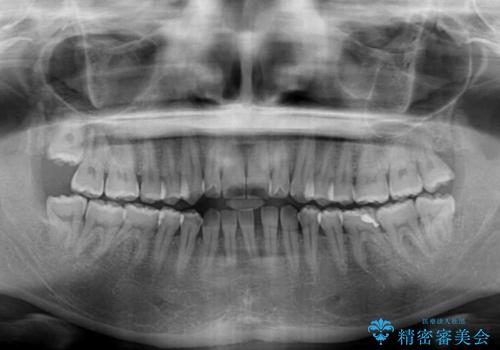

下顎前歯が1本欠損しており、上下小臼歯はクロスバイトとなり、上下前歯の接触もないという不正咬合の状態でした。

クロスバイトはワイヤー矯正が得意とするところであり、上下前歯の非接触や開咬はインビザラインの得意とするところであるので、ワイヤー装置により事前にクロスバイトを改善し、その後にインビザラインにて仕上げていくこととしました。